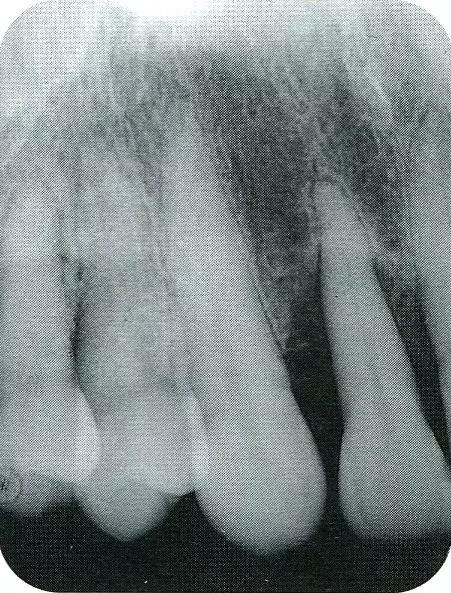

▲圖8-2  初診時的x片。尖牙遠中確認有垂直性骨缺損。